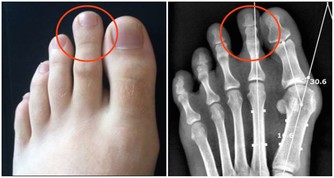

骨質疏鬆症的主要特徵是骨礦物質含量低下、骨強度降低、易發生骨折等。上了年紀的老人家走路駝背、身高降低,其實都是骨質疏鬆症的表現。

與此同時,骨質疏鬆症也被稱為“沉默的殺手”。因骨頭“變脆”,容易導致骨折。